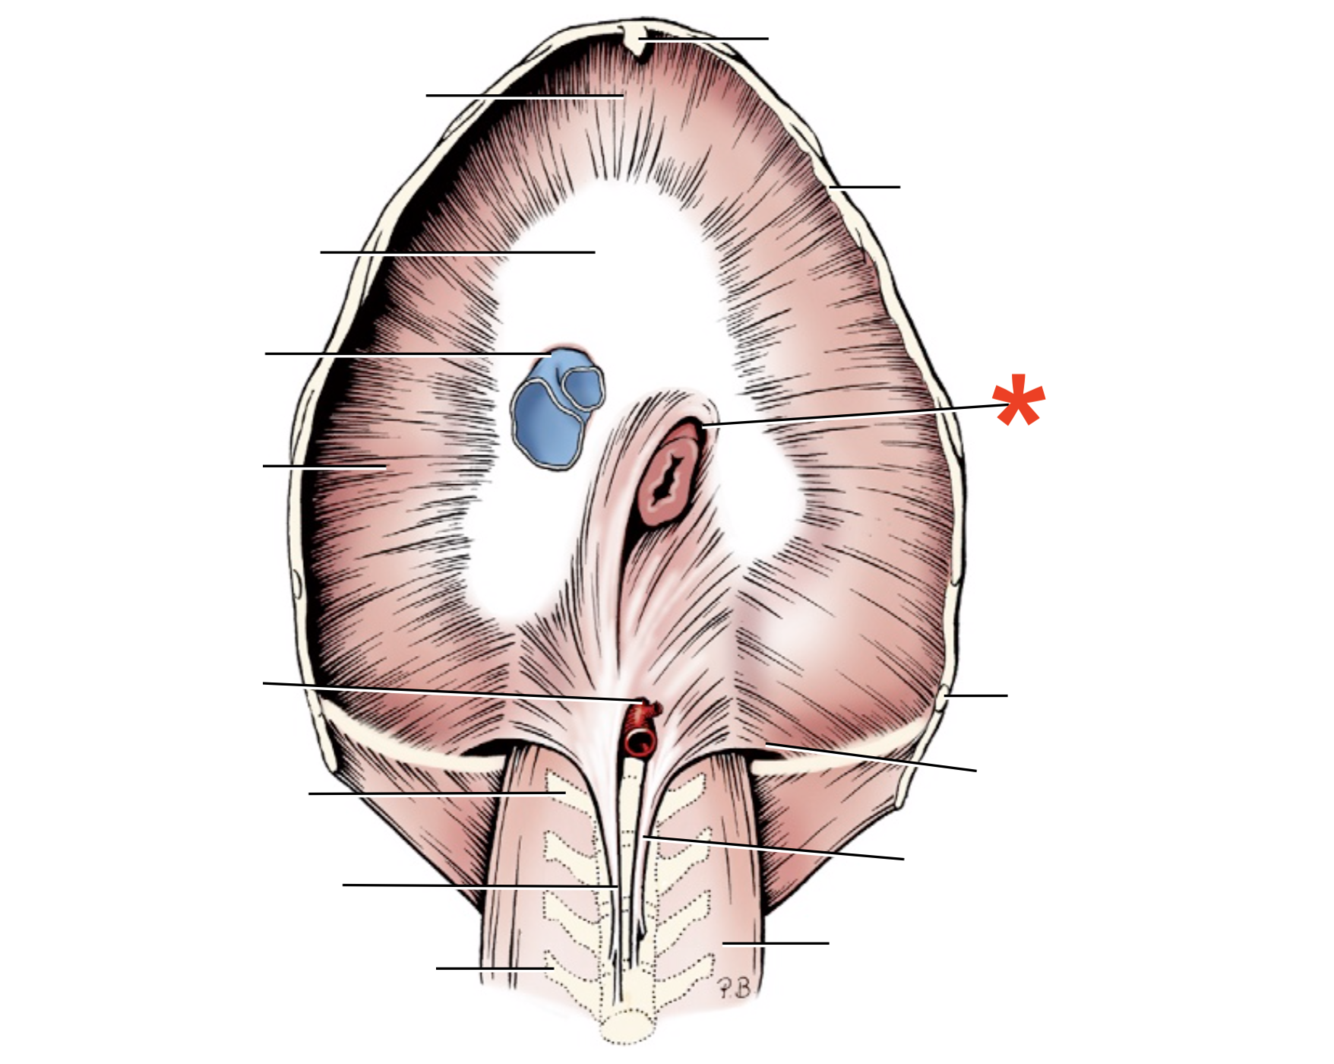

Name given to the most cranial part of the diaphragm.

Cupula Diaphragmatis

Q

Pars sternalis

Q

Foramen vena cavae

Q

Pars costalis

Q

Hiatus aorticus

Q

Arcus lumbocostalis

Q

Hiatus oesophagus

Q

Crus sinistrum

Q

Crus dextrum

Q

Centrum tendineum

Q

Corona muscularis